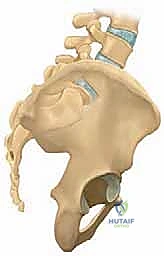

2. الدمج الخلفي الجانبي (Posterolateral Fusion - PLF)

بعد تحرير الأعصاب، يجب تثبيت العمود الفقري. في تقنية الدمج الخلفي الجانبي، يتم وضع مسامير من التيتانيوم (Pedicle Screws) في جذور الفقرات، وتوصيلها بقضبان معدنية قوية. ثم يتم وضع طعوم عظمية (Bone Grafts) - تؤخذ عادة من عظام الحوض للمريض أو من بنك العظام - على الأجزاء الجانبية للفقرات (Transverse Processes). بمرور الأشهر، ينمو العظم الجديد ليلحم الفقرات معاً ككتلة عظمية واحدة صلبة، مما يمنع أي حركة غير طبيعية.

3. دمج الفقرات بين الأجسام الفقرية (PLIF / TLIF)

في حالات الانزلاق عالي الدرجة، غالباً ما يتطلب الأمر دعماً إضافياً من الأمام (بين أجسام الفقرات). هنا يتألق الدكتور هطيف باستخدام تقنيات (PLIF - Posterior Lumbar Interbody Fusion) أو (TLIF - Transforaminal Lumbar Interbody Fusion).

في هذه التقنية، يتم استئصال القرص الغضروفي التالف بالكامل، ووضع قفص داعم (Cage) مصنوع من مادة الـ PEEK أو التيتانيوم، ومملوء بالطعوم العظمية، في مكان الغضروف. هذا الإجراء يعيد الارتفاع الطبيعي للفقرات، ويفتح مسارات الأعصاب بشكل ممتاز، ويوفر نسبة نجاح للدمج العظمي تقارب 100% لأنه يضع العظم في منطقة تتحمل ضغطاً ميكانيكياً عالياً مما يحفز نمو العظام.